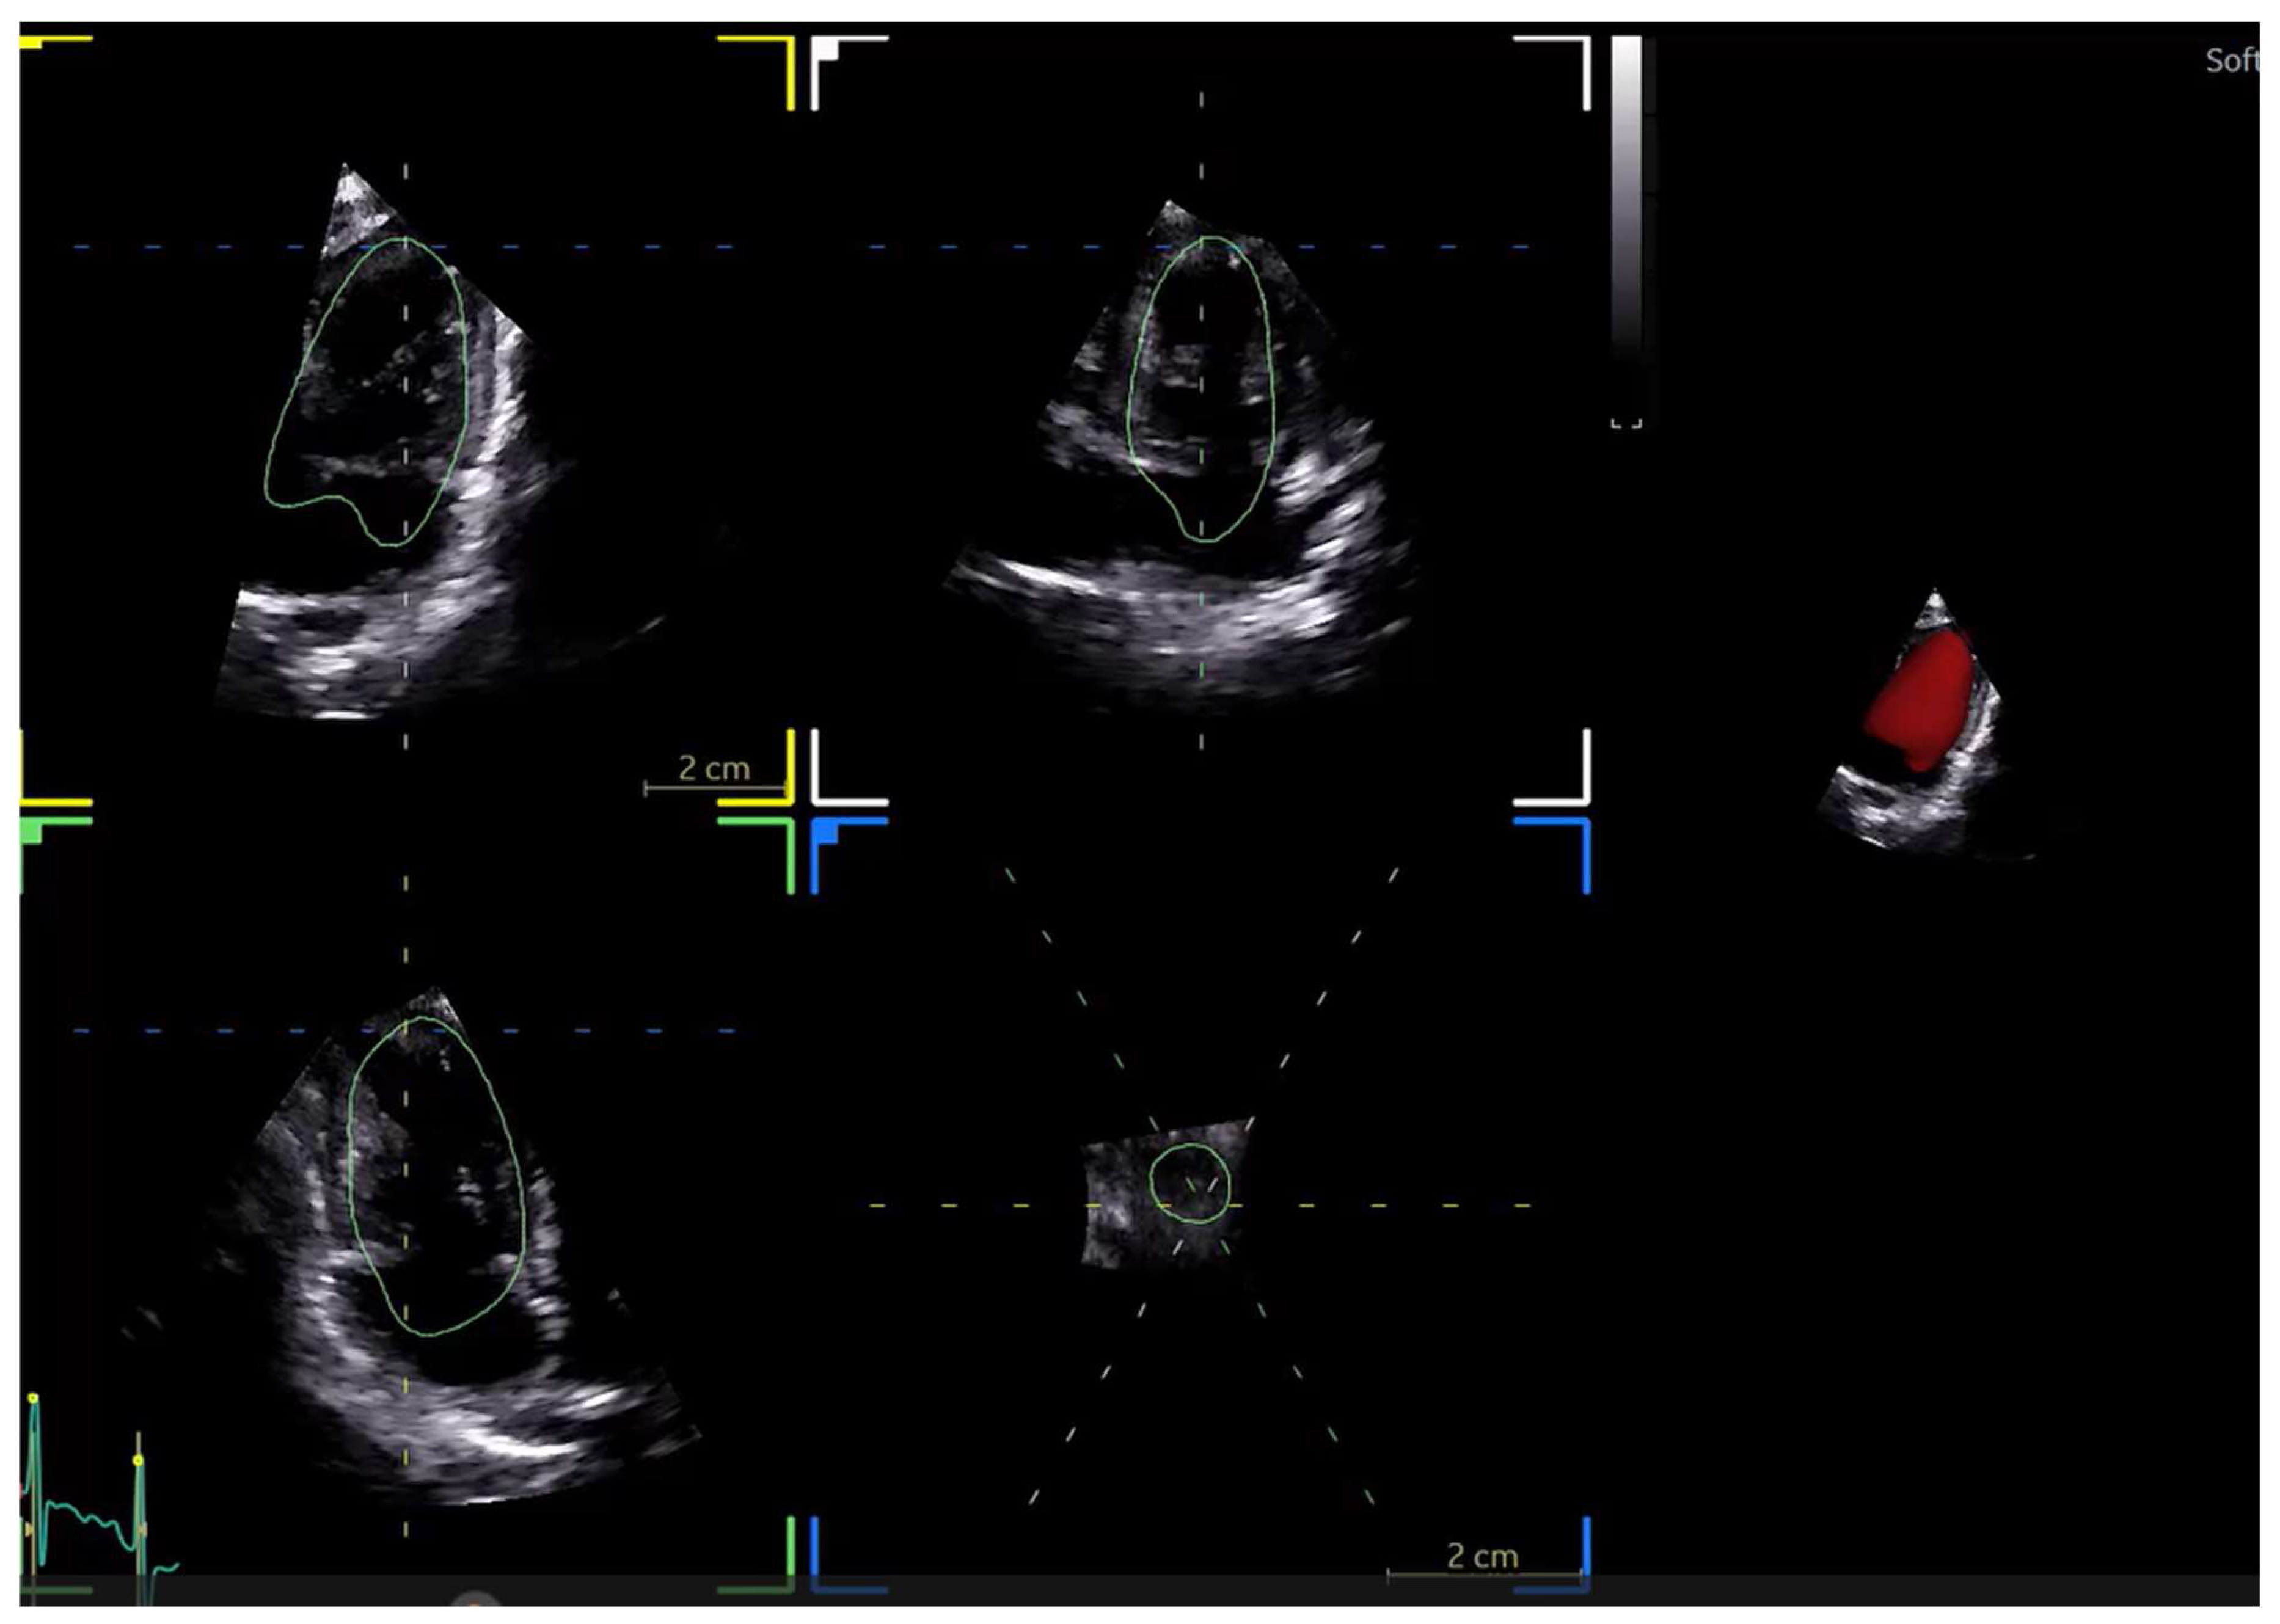

- Ahmad A, Shigemitsu S, Termachi Y, Windram J, Khoo N, Colen T, Eckersley L (2022) Comparing a knowledge-based 3D reconstruction algorithm to TomTec 3D echocardiogram algorithm in measuring left cardiac chamber volumes in the pediatric population. Echocardiography 39:1180–1189. [CrossRef]